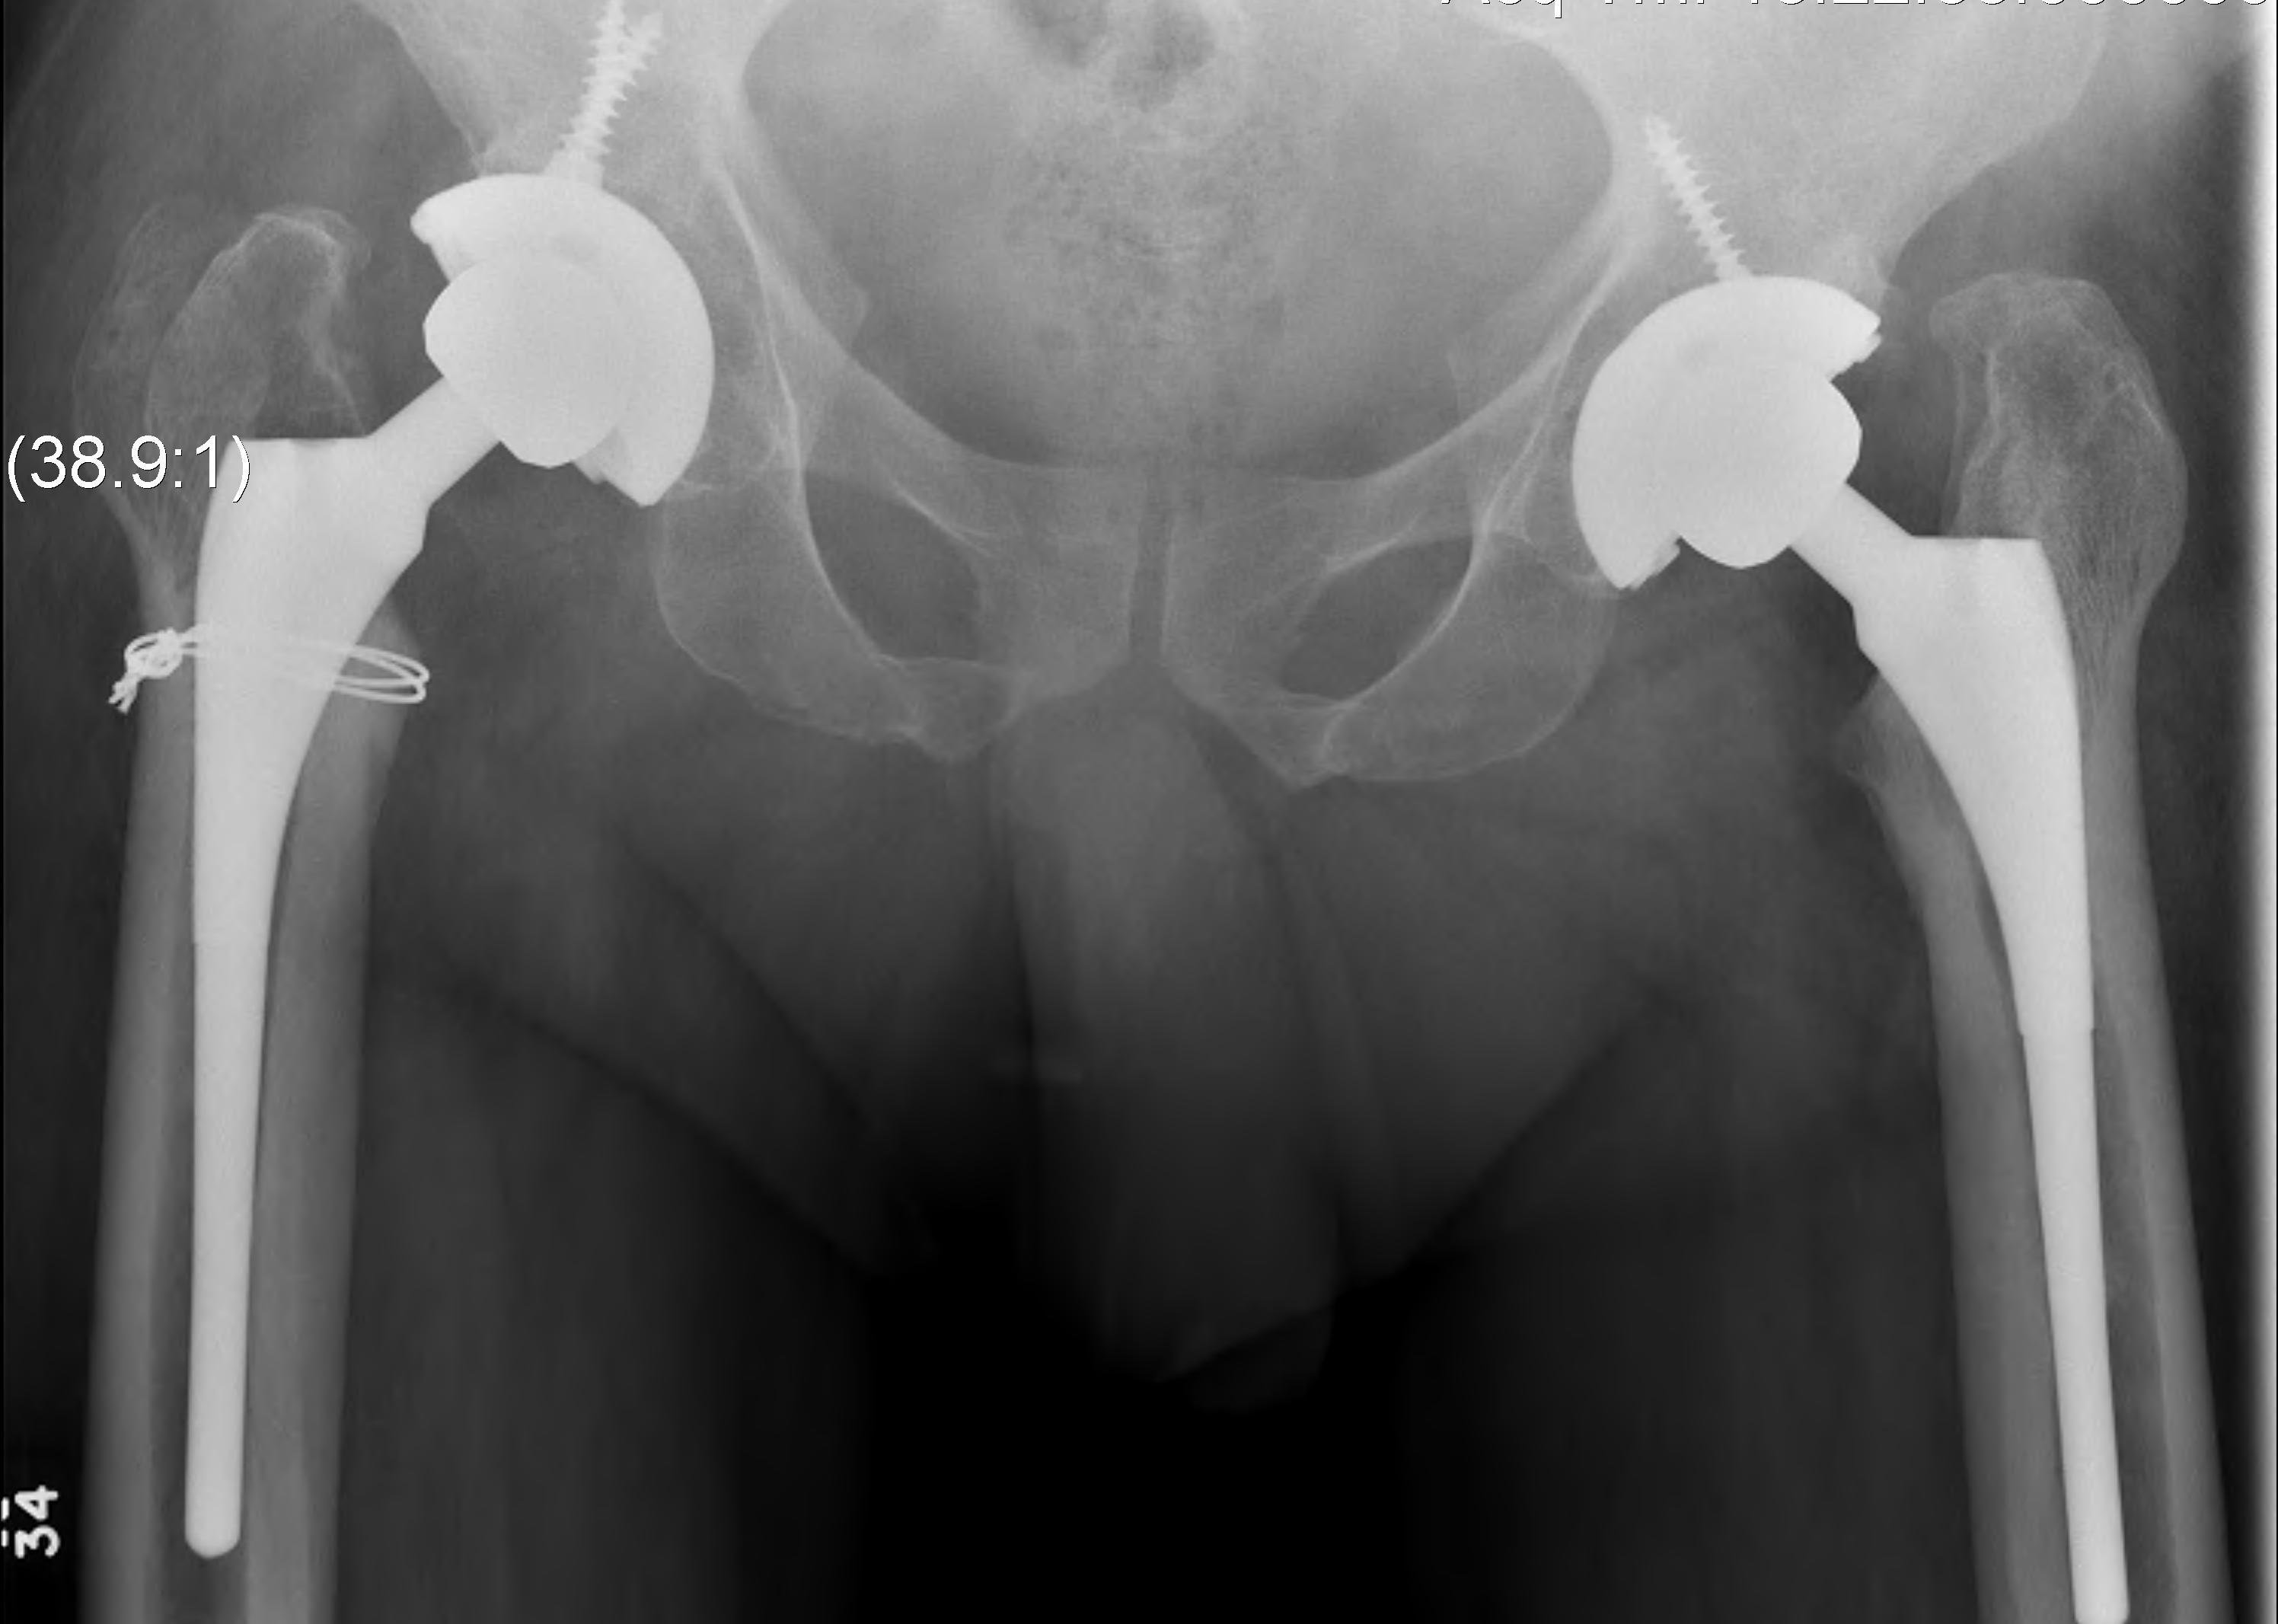

Technique

Option

- monoblock stem

- modular stem

Uncemented stem

Modular stem

Trochanteric slide